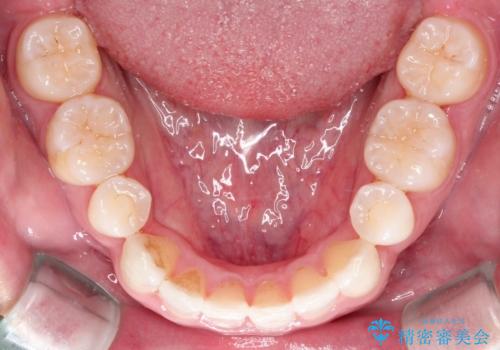

【インビザライン】笑った時の歯並びを綺麗にしたい

- 20代男性

- インビザライン

- 1年

- 笑った時の歯の見え方を綺麗にしたいことを主訴に来院されました。

インビザラインにて治療を行なっております。

シミュレーションを用いてることで患者さんと最終的なゴールを確認し行いながら治療を行うことができます。